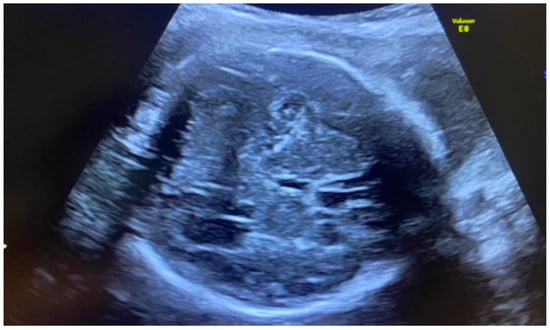

Whole fetal organs may be directly or indirectly affected by viral infection. Most of the time, the imaging signs are unspecific and may be associated with causes other than congenital CMV, genetic or not. Digestive tube abnormalities can be related in particular to the hyperechogenicity of the bowel (Figure 5), intrahepatic calcifications, and hepatosplenomegaly, as well as pleural effusion, fetal edema, ascites, or hydrops [64,65]. Splenomegaly is considered a common ultrasound finding related to congenital CMV infection. Researchers found that the examination of the splenic artery by Doppler evaluation may be used as a non-invasive marker for congenital CMV, probably related to impaired arterial blood flow [66]. Congenital infection may influence cardiac development, and signs such as cardiomegaly, the effusion of liquid in the pericardium, and calcifications may be highlighted [5].

Figure 5. Bowel hyperechogenicity.